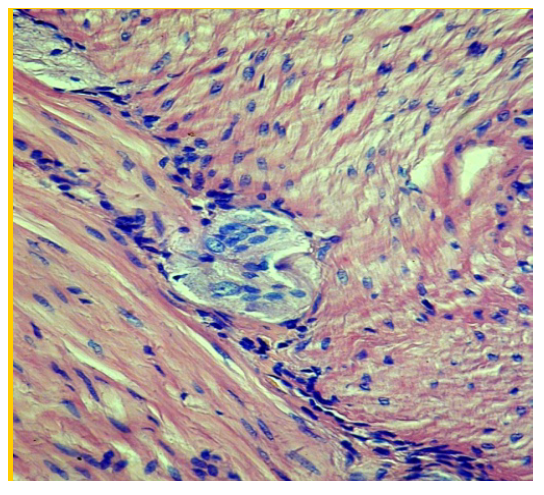

Гистоархитектоника слоев стенки двенадцатиперстной кишки была относительно сохранена. Отмечались уменьшение высоты ворсин и сглаженность рельефа слизистой оболочки. Покровный эпителий выглядел уплощенным, ядра клеток с базальным расположением, надъядерная часть с участками просветления, местами вакуолизирована. В апикальных отделах ворсинок отмечено уменьшение числа бокаловидных клеток, в базальных отделах ворсинок их число увеличивалось. На одну ворсину приходилось две, три крипты (рис. 1).

Рис. 1. Увеличение объема надъядерной части энтероцитов, очаговая вакуолизация цитоплазмы. Окраска гематоксилином и эозином × 40